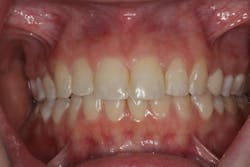

In time, the teeth began to remineralize, and the enamel started to look more normal. Given our limited time frame, at five weeks we included a home whitening regimen (Opalescence, Ultradent Products). The patient was still seen weekly for application of phosphoric acid and Remin Pro until her wedding day.

During week seven, we fixed her incisal edge fracture. A mylar strip was placed to protect the adjacent tooth, and the fractured edge was etched with Vococid for 15 seconds (figure 6). Following copious rinsing and drying, Futurabond U (Voco) was applied onto the enamel for 20 seconds, air-dried, and light-cured. Grandioso (Voco) in shade A2 was placed, contoured, and polished.

The patient was ecstatic with her new smile (figure 7). A five-year post-op photo shows stability of the result with no recurrence of the demineralized enamel (figure 8).